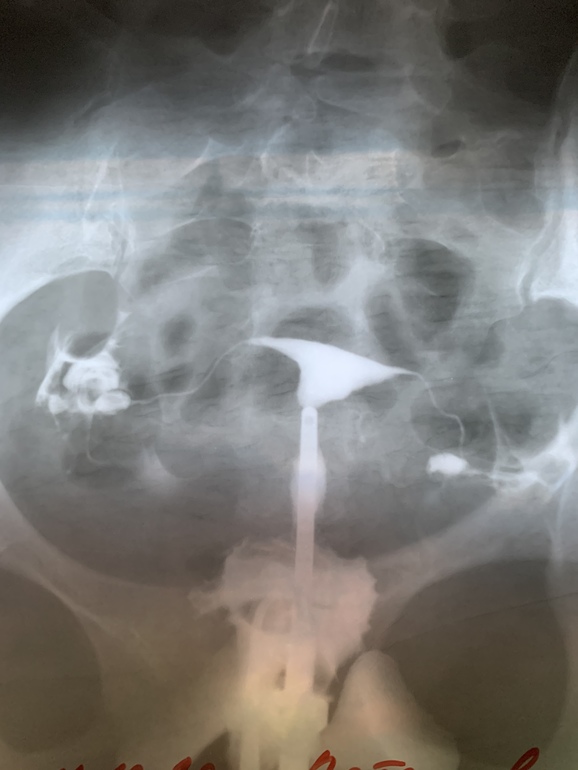

Снимки ГСГ, интерпретация результата

Девушки, привет! Выписалась я из больницы счастливая, обе трубы проходимы. Врач рассказала, о том что ГСГ чудодейственная процедура, которая имеет промывающий эффект. То есть от нее промываются мелкие спайки. И многие беременеют в первых циклах после ГСГ. Я с этими снимками еду к своему репродуктологу. А она говорит, что трубы проходимы лишь частично, что мало контраста проникло в брюшную полость. Сказала, если к весне не удастся забеременеть, отправит на лапароскопию...